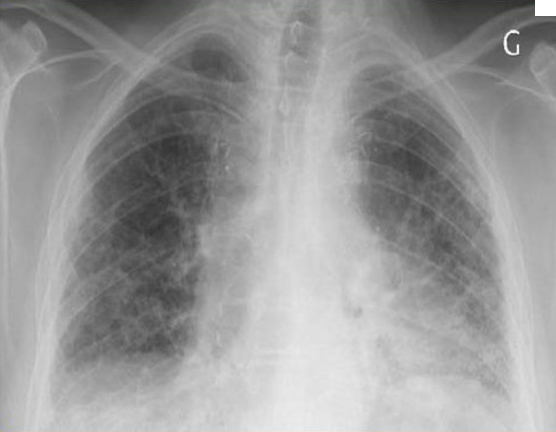

Question 7 : Un scanner thoracique a été réalisé ; interprétez-le :

Il s’agit ici d’un tableau de pneumopathie interstitielle diffuse ayant évolué vers la fibrose. La sémiologie des lésions élémentaires du syndrome interstitiel déjà décrit à la question 2 est associé à des signes de fibrose qui peuvent comprendre de manière générale deux grandes entités :

1) de la destruction parenchymateuse : typiquement les microkystes (rayon de miel) qui sont de petits « trous », avec paroi, à prédominance sous-pleural

2) des distorsions architecturales dont la plus connues et fréquente et la bronchectasie de traction (différent de la dilatation des bronches qui est une maladie inflammatoires des bronches, la bronchectasie de traction correspond juste à une distorsion de la bronche par traction interstitielle)

Concernant l’origine de la PID, l’on s’orientera ici préférentiellement vers l’asbestose car le scanner montre des images plutôt en faveur de pneumopathie interstitielle commune (PIC) (absence de verre dépoli) et l’alvéolite est neutrophilique ; dans le cadre d’une PID médicamenteuse, l’alvéolite est plutôt lymphocytaire voire éosinophilique et les images plutôt en faveur d’une pneumopathie interstitielle non spécifique (PINS) (verre dépoli+++) et dans la PID de la dermatopolymyosite si l’alvéolite est plutôt neutrophilique ou lymphocytaire, le scanner montre le plus souvent des images de pneumopathie interstitielle non spécifique (PINS) également.

La PIC et la PINS sont des tableaux radiologiques décrit ci-dessous :